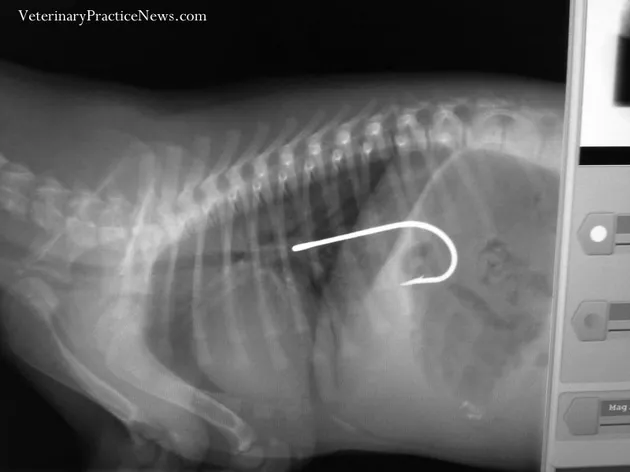

Dari kesemuanya, mungkin ini yang lumayan bikin ngilu. Seekor anjing bernama Elvis memakan hati ayam yang ternyata sudah dipasangi kail oleh pemiliknya. Hati ayam tersebut rencananya akan digunakan sebagai umpan pancing. Elvis dibawa ke The Animal Clinic PSC untuk dilakukan tindakan operasi, dan berhasil selamat.

Hak Cipta: Veterinary Practice News